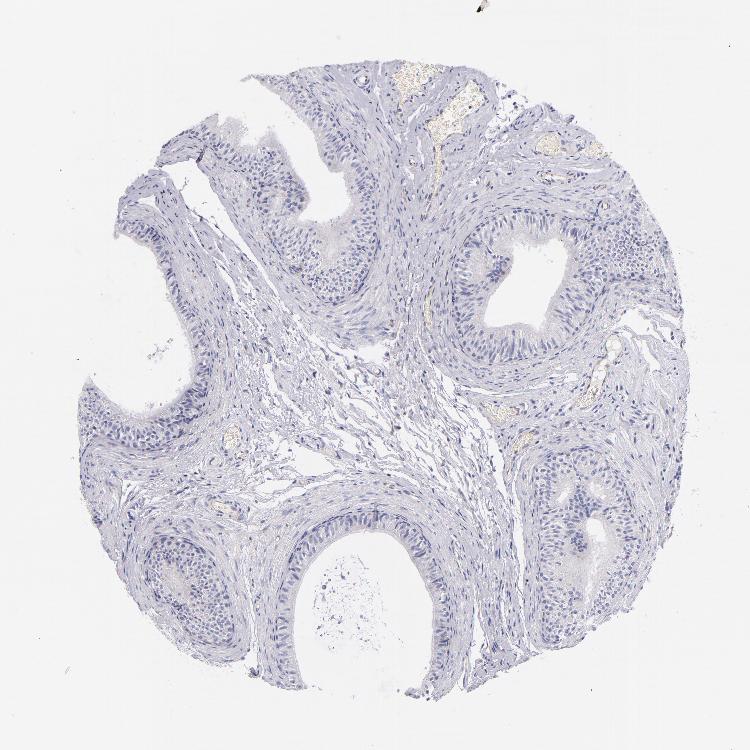

NOS3